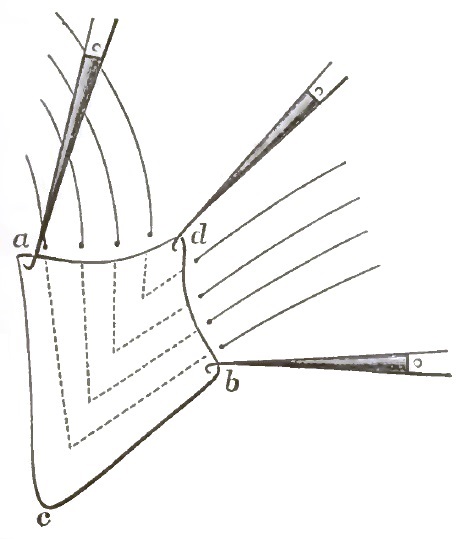

| 13. | THE SUTURES IN PLACE |

| 14. | THE VAGINAL SUTURES TWISTED |